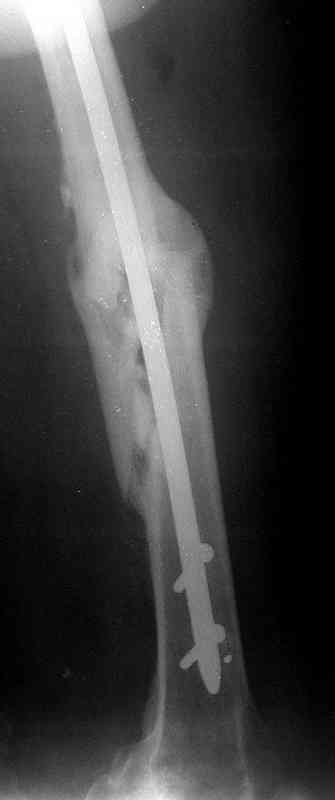

В общем, план тот же - удаление, закрытый реостеосинтез стержнем с блокированием. Лучше с коррекцией не только оси, но и длины. По деталям - может быть много нюансов. Можно удалить стержень, наложить интраоперационный дистрактор, лучше спицевой, растянуть сколько получится, заштифтовать с коррекцией оси с помощью отклоняющих (Poller) спиц/винтов, и в этом "напряжении растяжения" статически запереть. Какие имплантаты доступны?

Абсолютно согласен с А.Челноковым, что метод выбора в данной ситуации: удаление штифта, антеградное рассверливание и реостеосинтез массивным штифтом... и не обязательно блокированным... на мой взгляд, можно использовать и общепринятый штифт типа Кюнчера.

Удалить, исправить ось, рассверлить, заштифтовать блокируемым гвоздем.

Оптимально - титановый блокируемый дистально и проксимально штифт, с анатомической кривизной, диаметром 12-14 мм. Каннюлированный или солидный - непринципиально.

Альтернатива - малоинвазивно длинную LC-LCP.

1) Биомеханически штифт в центре кости выгоднее пластины снаружи

2) Технически штифтование проще

3) Штифтование менее травматично для мягких тканей

4) На штифте рекомендуем полную нагрузку сразу

БЛОКИРУЕМЫЙ ШТИФТ1

Конечно.

Интрамедулляный гвоздь, безусловно. Перимущества А.Семенистый в основном перечилил. В чем конкретно остаются сомнения, чтобы не повторяться?

Можно. Ввести отклоняющую спицу или винт в передне-заднем направлении примерно посредине поперечника бедра, на 4-6 см ниже перелома.

Сегодня фотография открылась...беру свои слова назад: перелом явно в расширенном участке бедра. Целесообразней всего динамический блокирующий остеосинтез.

Учитывая смещения отомков по длине (хоть и 1,5 см, но все же..), очевидное ротационное смещение (видно даже по Р-мам) самым правильным, на мой взгляд, решением было бы: наложение аппарата Илизарова на бедро с остеотомией бедренной кости и исправлением ротационной деформации. Дистракция на аппрате пару недель и последующий блокирующий остеосинтез. У нас в клинике был один пациент с практически идентичной историей (укорочение конечности было значительно больше), которому мы выполнили такую операцию (блокирующий остеосинтез был выполнен без рассверливания костно-мозгового канала). В настоящее время больной работает, прыгает с парашютом, периодически звонит и благодарит за лечение.

Больной А., 28 лет, поступил в НИИ им. Н.В. Склифосовского 22.12.99 после падения на улице. Жалобы на боли в области левого тазобедренного сустава и левом бедре. Из анамнеза следовало, что 20.06 во время прыжка с парашютом у него возник закрытый оскольчатый перелом средней трети левой бедренной кости со смещением отломков, по поводу чего в одной из ЦРБ Московской области через 3 дня после травмы был произведен открытый интрамедуллярный остеосинтез штифтом типа Кюнчера.

по его наружной поверхности послеоперационный рубец - рана зажила первичным натяжением. При измерении длины бедер обнаружено укорочение левого бедра на 4,5 см. На рентгенограммах этого бедра: ось конечности правильная, отмечается захождение основных костных фрагментов по длине, проксимальный конец штифта выступает слишком медиально и высоко относительно большого вертела, периостальная мозоль незначительна.22.12 - через 6 месяцев после операции, произведенной в ЦРБ, нами по поводу замедленно консолидирующего перелома левой бедренной кости с ее абсолютным укорочением под наркозом произведена операция: удаление штифта, закрытый блокирующий интрамедуллярный остеосинтез перелома левого бедра штифтом без рассверливания (UFN) длиной 40 см, диаметром 10 мм с блокированием только проксимальных отверстий (динамический остеосинтез). Наложен аппарат Илизарова на 4 полукольцах с целью удлинения укороченного бедра. Послеоперационное течение без особенностей. Ежедневно осуществляли дистракцию отломков на 1 мм. Через 3 недели после операции больной выпи-сан на амбулаторное лечение с продолжением дистракции отломков. В течение 1,5

месяцев дистракции укорочение левого бедра удалось полностью устранить. 22.02.00, т.е. через 2 месяца после повторного остеосинтеза, больному произведено дистальное блокирование штифта двумя винтами и демонтирован аппарат Илизарова. В течение 2 недель после операции больной ходил с помощью костылей, потом 2 недели с тростью. Опороспособность и функция оперированной конечности полностью восстановились через 4 недели после операции.

Фиксаторы удалены через 12 месяцев после операции, выполненной по поводу замедленной консолидации перелома бедра с его укорочением.